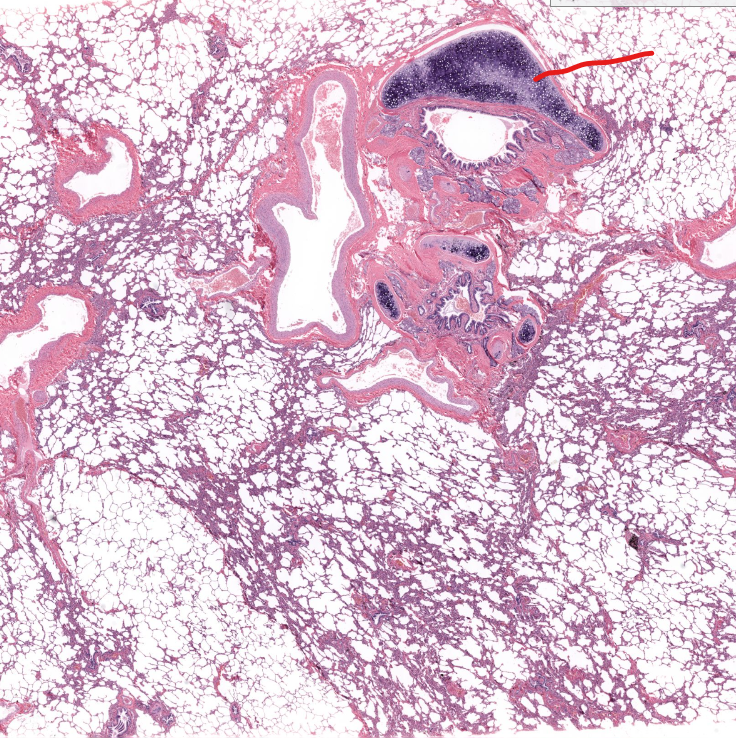

(organ)

lung

bronchiole cartilage of lung

terminal bronchiole of lung

(red line)